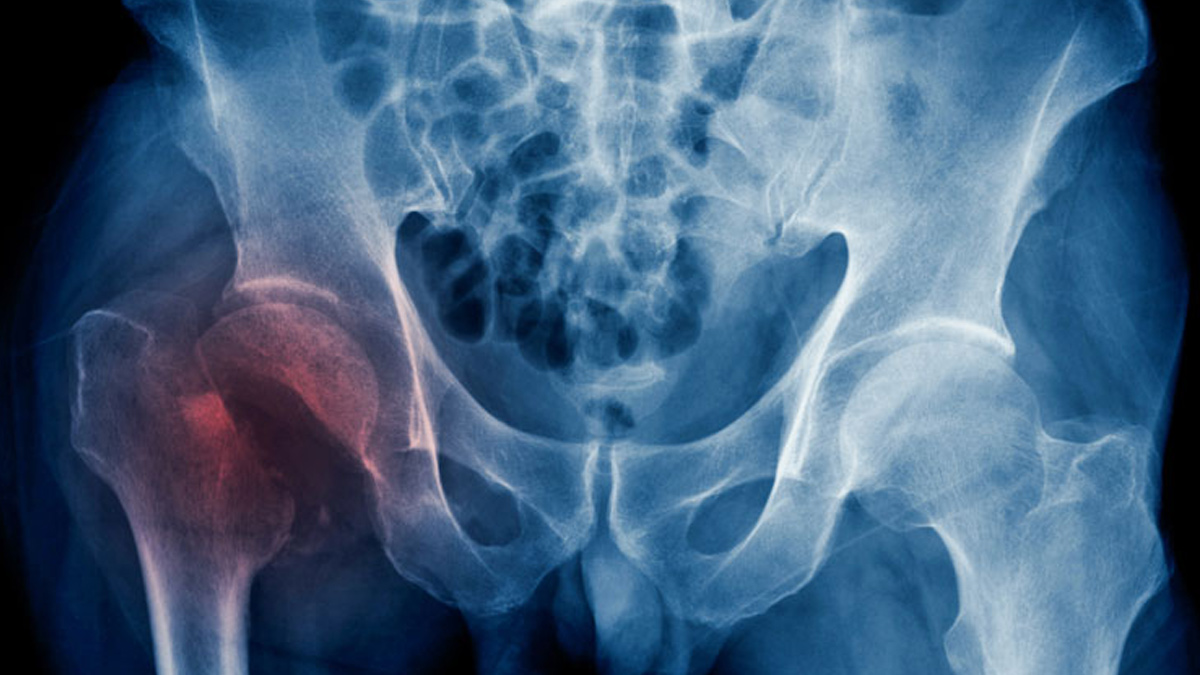

- Bone Density: Women with diabetes showed a 4.4% higher bone density in the hip and similar increases in other areas like the femoral neck and lumbar spine. However, there was a slight decrease in density in other parts of the spine.